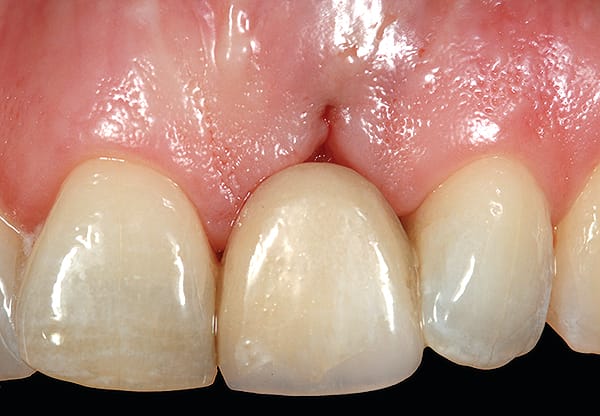

Before a clinician can decide on treatment, a diagnosis must be made whether the implant is healthy or not, meaning normal bone levels around the implant. Another decision of concern was whether to retain the dental implant. It was determined that the implant was healthy, however the recession defect was due to an overcontoured custom abutment secondary to excessive facial implant angulation (Figure 3). The tendency for most surgeons when presented with such a recession defect is to think of a “root” coverage type surgical procedure. Patients with a thin or intermediate phenotype may not respond well to such a technique. It was also mentioned previously that an exposed implant abutment is absent of blood supply and may be contaminated with endotoxins that would constrain the predictability of healing with a coronal positioned connective tissue flap. One of the tactics to predictably ensure primary flap closure of the defect is to “decoronate” or bury the implant12,13 by removing the existing implant abutment and placing a surgical cover screw (Figure 4). Consequently, the soft tissues will heal and cover the head of the implant—“nature’s connective tissue graft” or spontaneous in-situ gingival augmentation. A resin-bonded–retained bridge was used as a provisional transitional restoration (Figure 5 and Figure 6). After a 2-week period, closure of the tissue was evident but de-epithelialization was required to ensure completion (Figure 7). Three-months post-ridge healing, sounding to the implant head with a periodontal probe revealed 5 mm of coronal soft tissue thickness (Figure 8). It was then decided that a secondary ridge augmentation procedure was not necessary, only second-stage implant uncovering surgery was needed with a crestal incision biased toward the palate. The shape of the patient’s pre-existing abutment was modified creating a flat facial contour, disinfected, and replaced as a provisional abutment (Figure 9). The original crown was also used as a temporary following an acrylic reline (Figure 10). After 1-month post-implant exposure, a new acrylic provisional restoration was fabricated and used to re-shape and sculpt the soft tissues to match those of the contralateral natural tooth14 (Figure 11). The flat contour concept of the abutment restoration is followed throughout the definitive abutment (Figure 12) and crown restoration (Figure 13 and Figure 14). Figures 15 and 16 show the intraoral and smile view of this patient, respectively, receiving remedial treatment at 5-years post-surgical treatment.